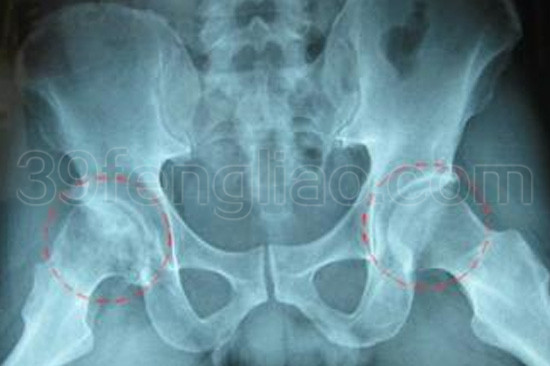

股骨头坏死为常见的骨病之一。它的主要症状:第一,疼痛。疼痛可为间歇性或持续性,行走活动后加重,有时为休息痛。疼痛多为针刺样、钝痛或酸痛不适等,常向腹股沟区、大腿内侧、臀后侧和膝内侧放射,并有该区麻木感。第二,关节僵硬与活动受限。患髋关节伸屈不利、下蹲困难、不能久站、行走鸭子步。早期症状为外展、外旋活动受限明显。第三,跛行。为进行性短缩性跛行,因髋痛及股骨头塌陷,或晚期出现髋关节半脱位所致。早期往往出现间歇性跛行,儿童患者则为更为明显。第四,体征。局部深压痛,内收肌点压痛,下肢发肿,4字试验阳性,A1 1 is征阳性等,有的息肢短缩,肌肉萎缩等。第五,X线表现。骨纹理细小或中断、股骨头囊肿、硬化、扁平或塌陷。

六、典型病例

研究院主办的第六期全国辩证无痛中医蜂疗实用新特技能培训班期间,有名学员贾先生正为股骨头坏死患者,贵州人,48岁,因大量用激素患该病五年,拄杖四年,保护性跛行、下蹲困难、下肢浮肿,放射性大腿内侧疼痛、髋关痛、下肢短缩畏寒等。未接受置换术,经本院按上法治疗一段时间后,甩掉了拐杖,上述症状均明显减轻或消失。患者做梦也没想到有如此显著疗效,后来能与家人游泳了。患者自述:这在当初看来都是奢望。后继续依此法内外治疗致愈。